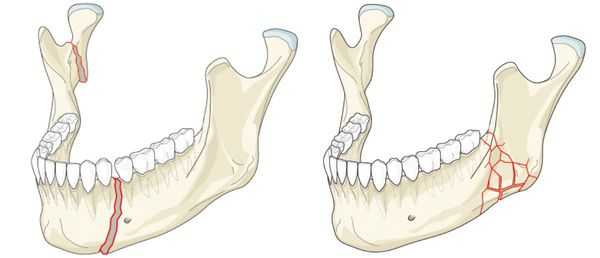

Переломы нижней челюсти возникают в месте приложения травмирующей силы (прямые) и вследствие перегиба (отраженные). Чаще бывают переломы в области клыков, резцов, углов и шеек, реже - венечного отростка. Бывают одиночные, двойные и множественные переломы. Переломы нижней челюсти отличаются разнообразием смещения отломков, что связано с действием мышечной тяги; при переломе тела челюсти смещение выражено резче при расположении линии перелома ближе к углу, чем к подбородку. Переломы в области зубного ряда, как правило, открытые.

Что касается локализации переломов, наиболее частой областью перелома является угол нижней челюсти; затем следуют переломы мыщелковых отростков, коренных зубов и подбородочного отдела. Срединные переломы встречаются реже, что объясняется толщиной челюсти в этой области.